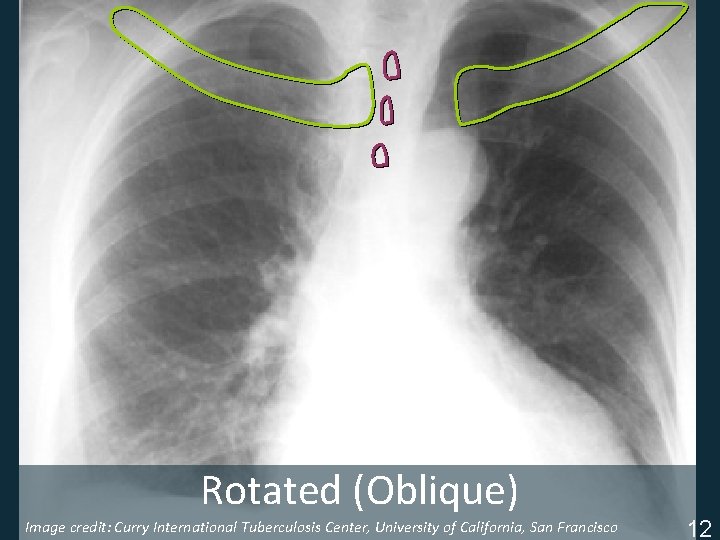

Rotated (Oblique) Image credit: Curry International Tuberculosis Center, University of California, San Francisco ISTC TB Training Modules 2009 12